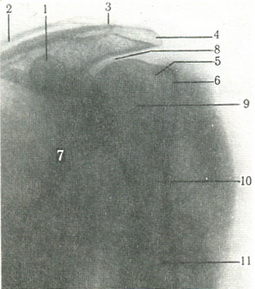

На знімку плечового суглоба в задній проекції головка плечової кістки видно в профіль без нашарування тіней інших кісток (рис. 124). Контури головки і тінь великого горбка видно чітко, а тінь малого горбка нашаровується на тінь шийки плечової кістки. Кут між віссю епіфіза та діафіза дорівнює 130° (див. схему). Суглобова западина лопатки має два контури, причому внутрішній більш товстий.

124. Рентгенограма в задній проекції лівого плечового суглоба. Пунктиром показано зміна кута між віссю головки і діафіза плечової кістки (по Л. Д. Линденбратену). 1 - клювовидный відросток лопатки; 2 - ключиця; 3 - ключично-акроминальное зчленування; 4 - акромион; 5 - анатомічна шийка плечової кістки; 6 - великий горбок плечової кістки; 7 - лопатка; 8 - суглобова западина лопатки; 9 - головка плечової кістки; 10 - хірургічна шийка плечової кістки; 11 - діафіз плечової кістки. |